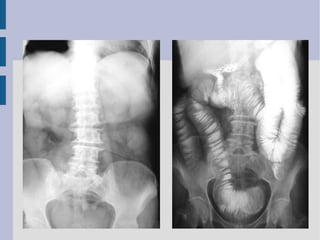

Este documento presenta un caso clínico de un hombre de 35 años con dolor abdominal y vómitos durante 24 horas. Describe las posibles causas de dolor abdominal difuso como apendicitis, pancreatitis aguda u obstrucción intestinal. Los hallazgos de rayos X e imágenes de TC muestran dilatación del intestino delgado, sin líquido libre abdominal ni neumoperitoneo. Las causas más frecuentes de obstrucción intestinal mecánica en adultos incluyen adherencias, invaginación intestinal, vólvulo y masas. El documento también